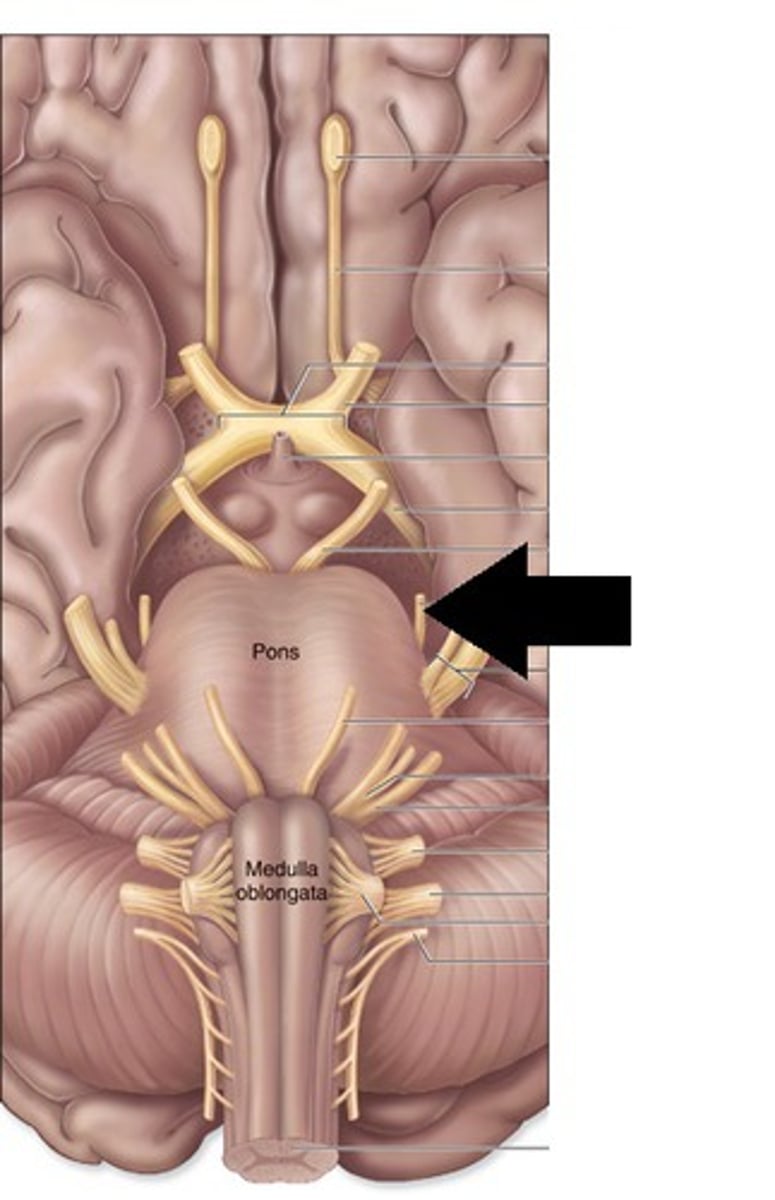

Which cranial nerves arise from the medulla? (and pontomedullary junction)

6-10, 12

name the groove

pontomedullary junction

general portion of the medulla

open medulla

general portion of the medulla

closed medulla

pyramids

ventral median fissure

pyramidal decussation

C

inferior cerebellar peduncles

cuneate tubercle

gracilis tubercle

cuneatus tract

gracilis tract

obex

What is the superior boundary of the pons?

What is the inferior boundary of the pons?

pontomedullary junction

middle cerebellar peduncles

What is the only cranial nerve that attaches to the pons?

CN V